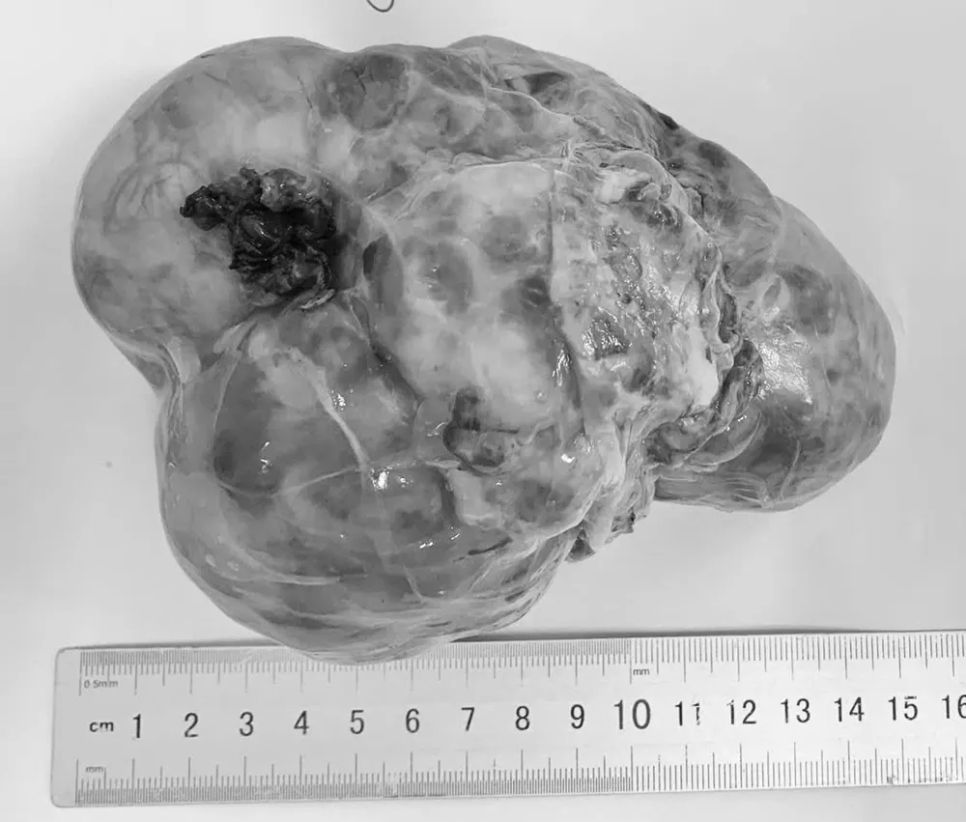

2 ngày gần đây, Khoa Ngoại, Bệnh viện Phụ sản – Nhi Đà Nẵng tiếp nhận và điều trị 3 trường hợp u ổ bụng ở trẻ em đến từ Quảng Ngãi. Em D.N.T.L. (14 tháng tuổi) mắc u nguyên bào thận; em N.K.H. (4 tuổi) mắc u nguyên bào thần kinh và em D.N.B.N. (5 tháng tuổi) bị u quái ổ bụng.

Tất cả các trường hợp đều được phát hiện khi tuổi còn nhỏ nhưng khối u đã phát triển lớn hoặc đã di căn.

Nhiều trường hợp vừa qua, khi nhập viện, khối u ở các bệnh nhi đều đã có kích thước lớn, làm tăng độ phức tạp của phẫu thuật và ảnh hưởng đến quá trình điều trị lâu dài.